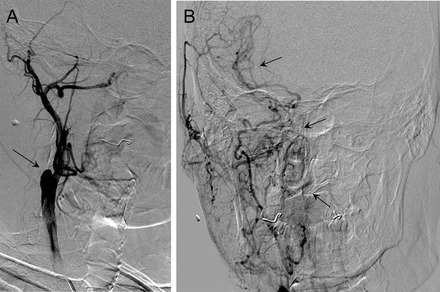

完整的血细胞计数和凝固测试是正常的。双颈动脉超声显示阻塞的初始部分右颈总动脉。左颈内动脉的收缩期峰值速度增加(146 cm / s)。右眼动脉流动逆转,增加(125 cm / s)。经颅多普勒超声显示逆流的A1段正确的大脑前动脉。右大脑中动脉流与并发操作并没有改变。脑部核磁共振血管摄影证实右侧颈总动脉的闭塞,没有其他异常。颈动脉闭塞并不完全解释眼睛疼痛,视力丧失,并排除其他原因(即。,arteriovenous malformations or fistulas), an arterial angiography was performed, which verified the presence of occlusion (图2)和显示增加抵押品血管化正确的眼周的区域(图2B);因此OIS的诊断。他规定120毫克/天,皮下注射依诺肝素治疗和口服强的松30毫克/天的剂量减少每周10毫克。后来他接受了全凝固。到6个月,疼痛已经解决,和视力丧失保持稳定。右眼眼压有所改善(20毫米汞柱)和保持不变的左眼(18毫米汞柱)。阿司匹林抗凝治疗然后切换到100毫克/天。